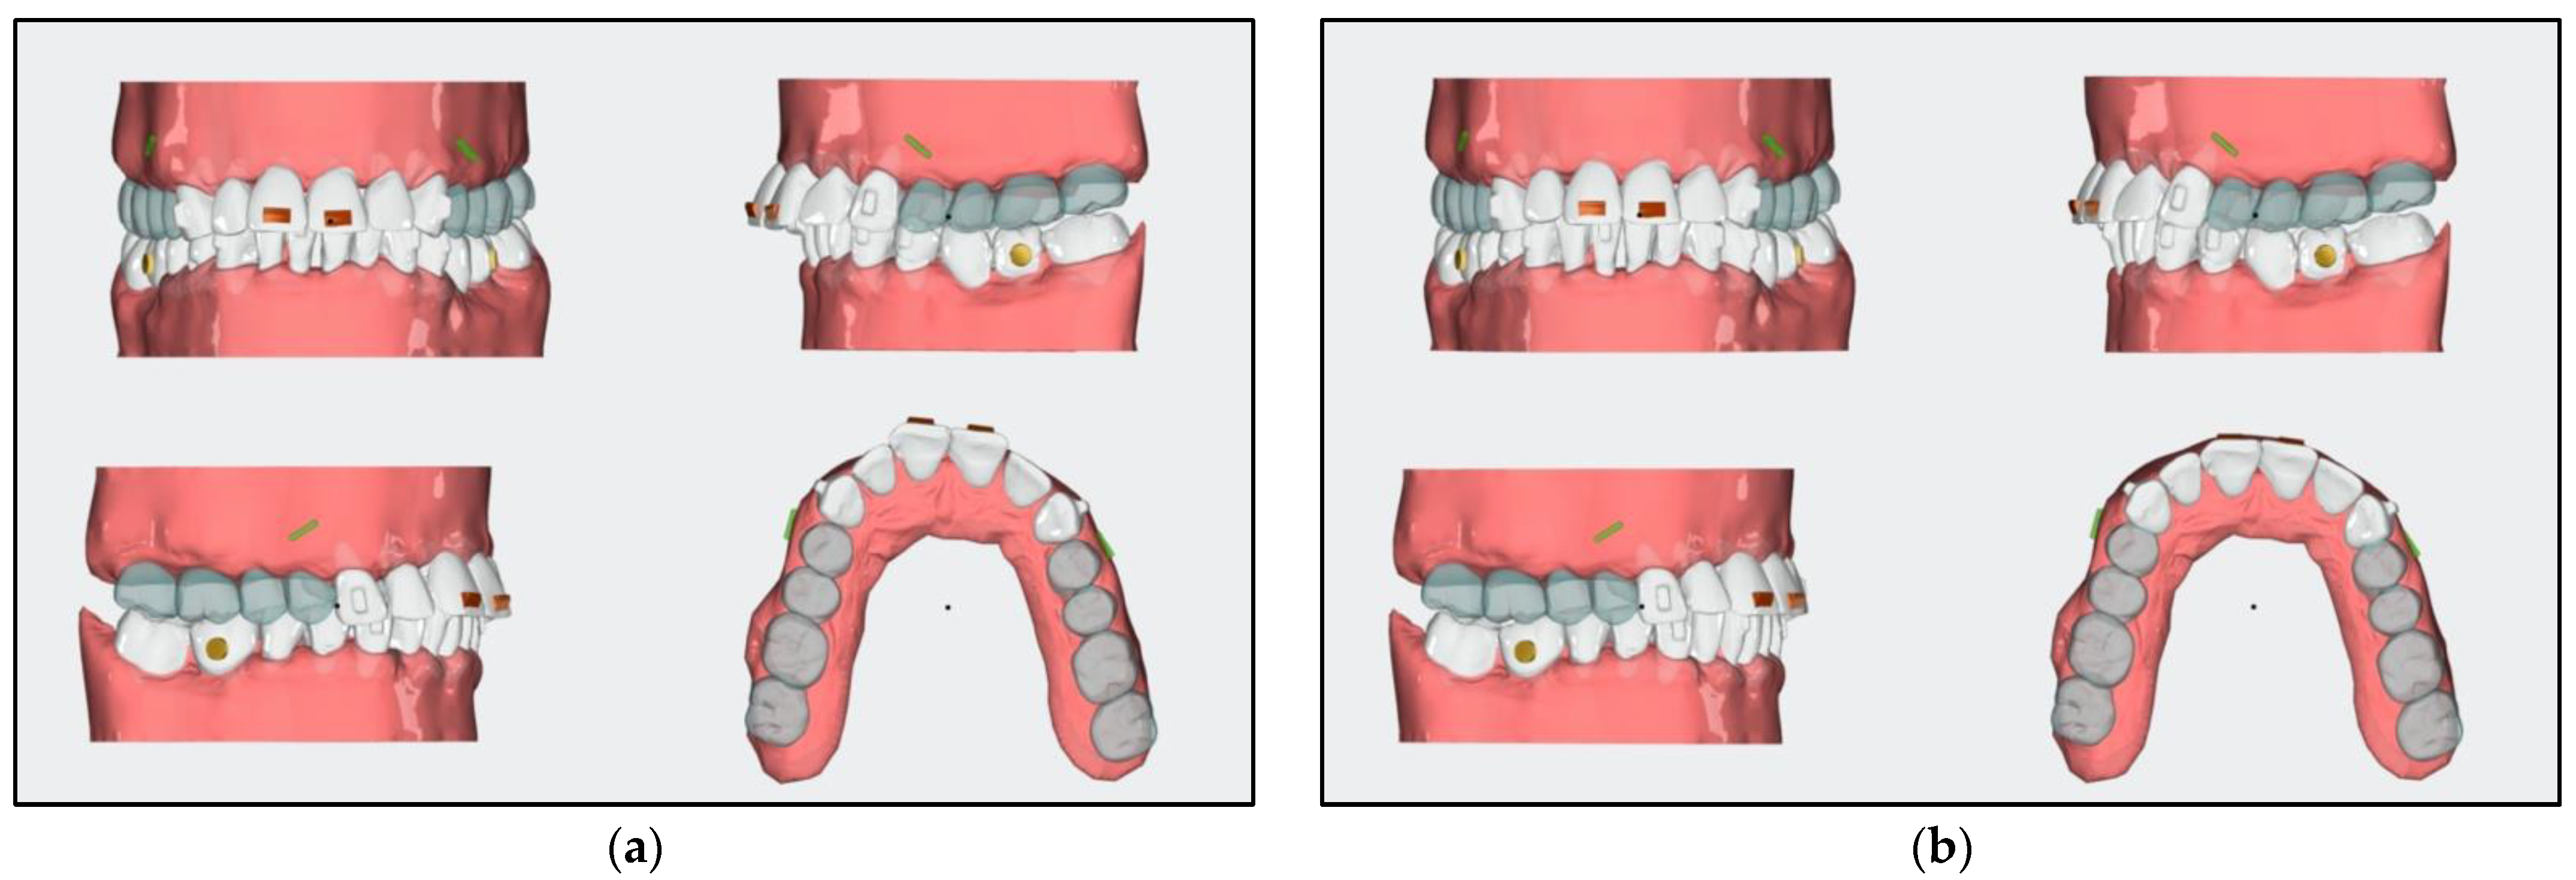

- For aligner stages 1 to 16, a mini screw in the area between teeth 34 and 36 was added for the distalization and uprighting of teeth 36 and 37.

- The distalization of teeth 16, 17, 26, and 27 was planned with aligners by adding Class II elastics of 6 Oz and a quarter of an inch.

- A horizontal attachment was added onto the temporary crown of tooth 21 for distalization using the implant as skeletal anchorage.

- After stage 16, rescanning should be carried out, and the space for the implant surgery of tooth 35 should be evaluated.